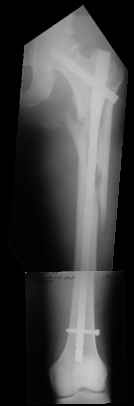

Few days ago I have posted an x-ray of severely comminuted Trochenteric # of Lt. Femur with sub-trochenteric extension of a male patient aged 65 years for opinion of fixation. Eight of you have kindly replied........

I choose Long Gamma Nailing and did it on 24.1.2006.

Now posting the post op x-rays for all of yours comments please. Don't hesitate to criticize me.

Congratulations. Virtually perfect. What reduction technique did you use? Looks like still traction table? To cavil to at least something looks like reduction is in microscopic varus - comparative x-rays can clear this - though only for academic interest with no clinical significance. Did you insert distal screws?